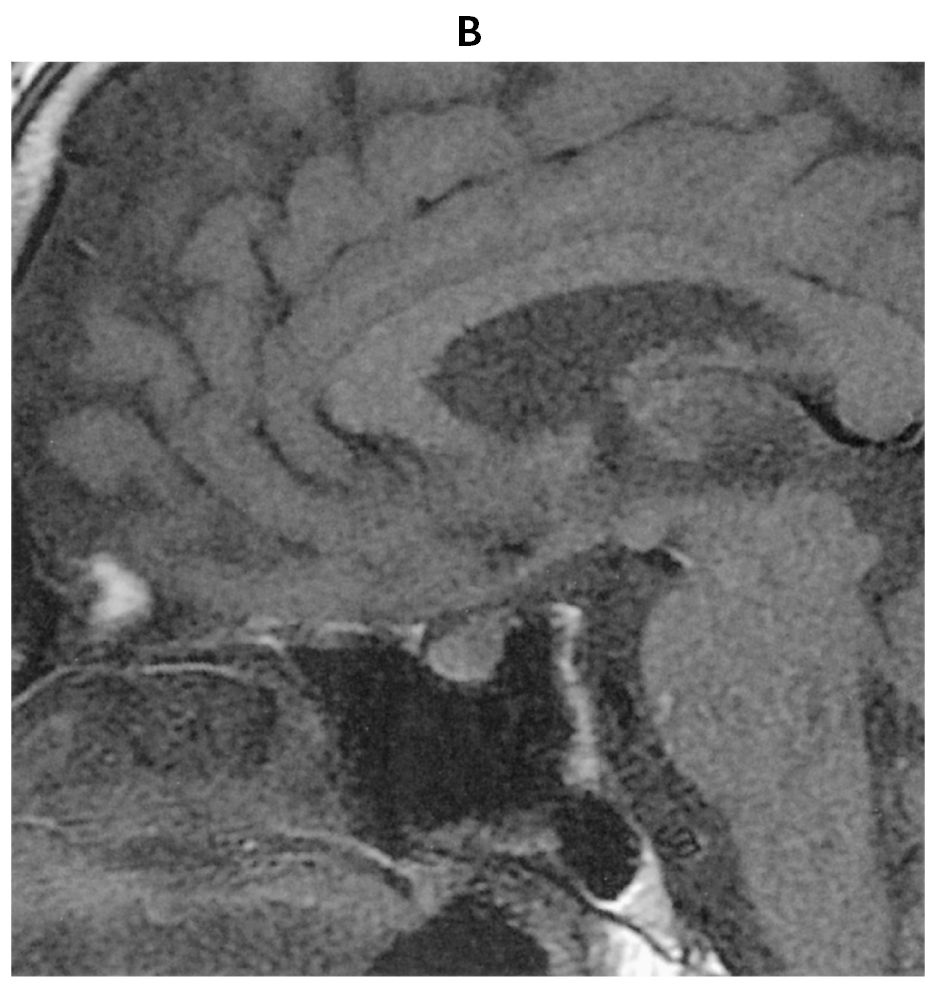

55歳の男性。口渇,多飲および多尿を主訴に来院した。尿量6~8L/日と著明な多尿が数週間続いている。口腔内は乾燥している。尿所見:蛋白(-),糖(-)。頭部造影MRIのT1強調冠状断像(A)と頭部単純MRIのT1強調矢状断像(B)とを下に示す。